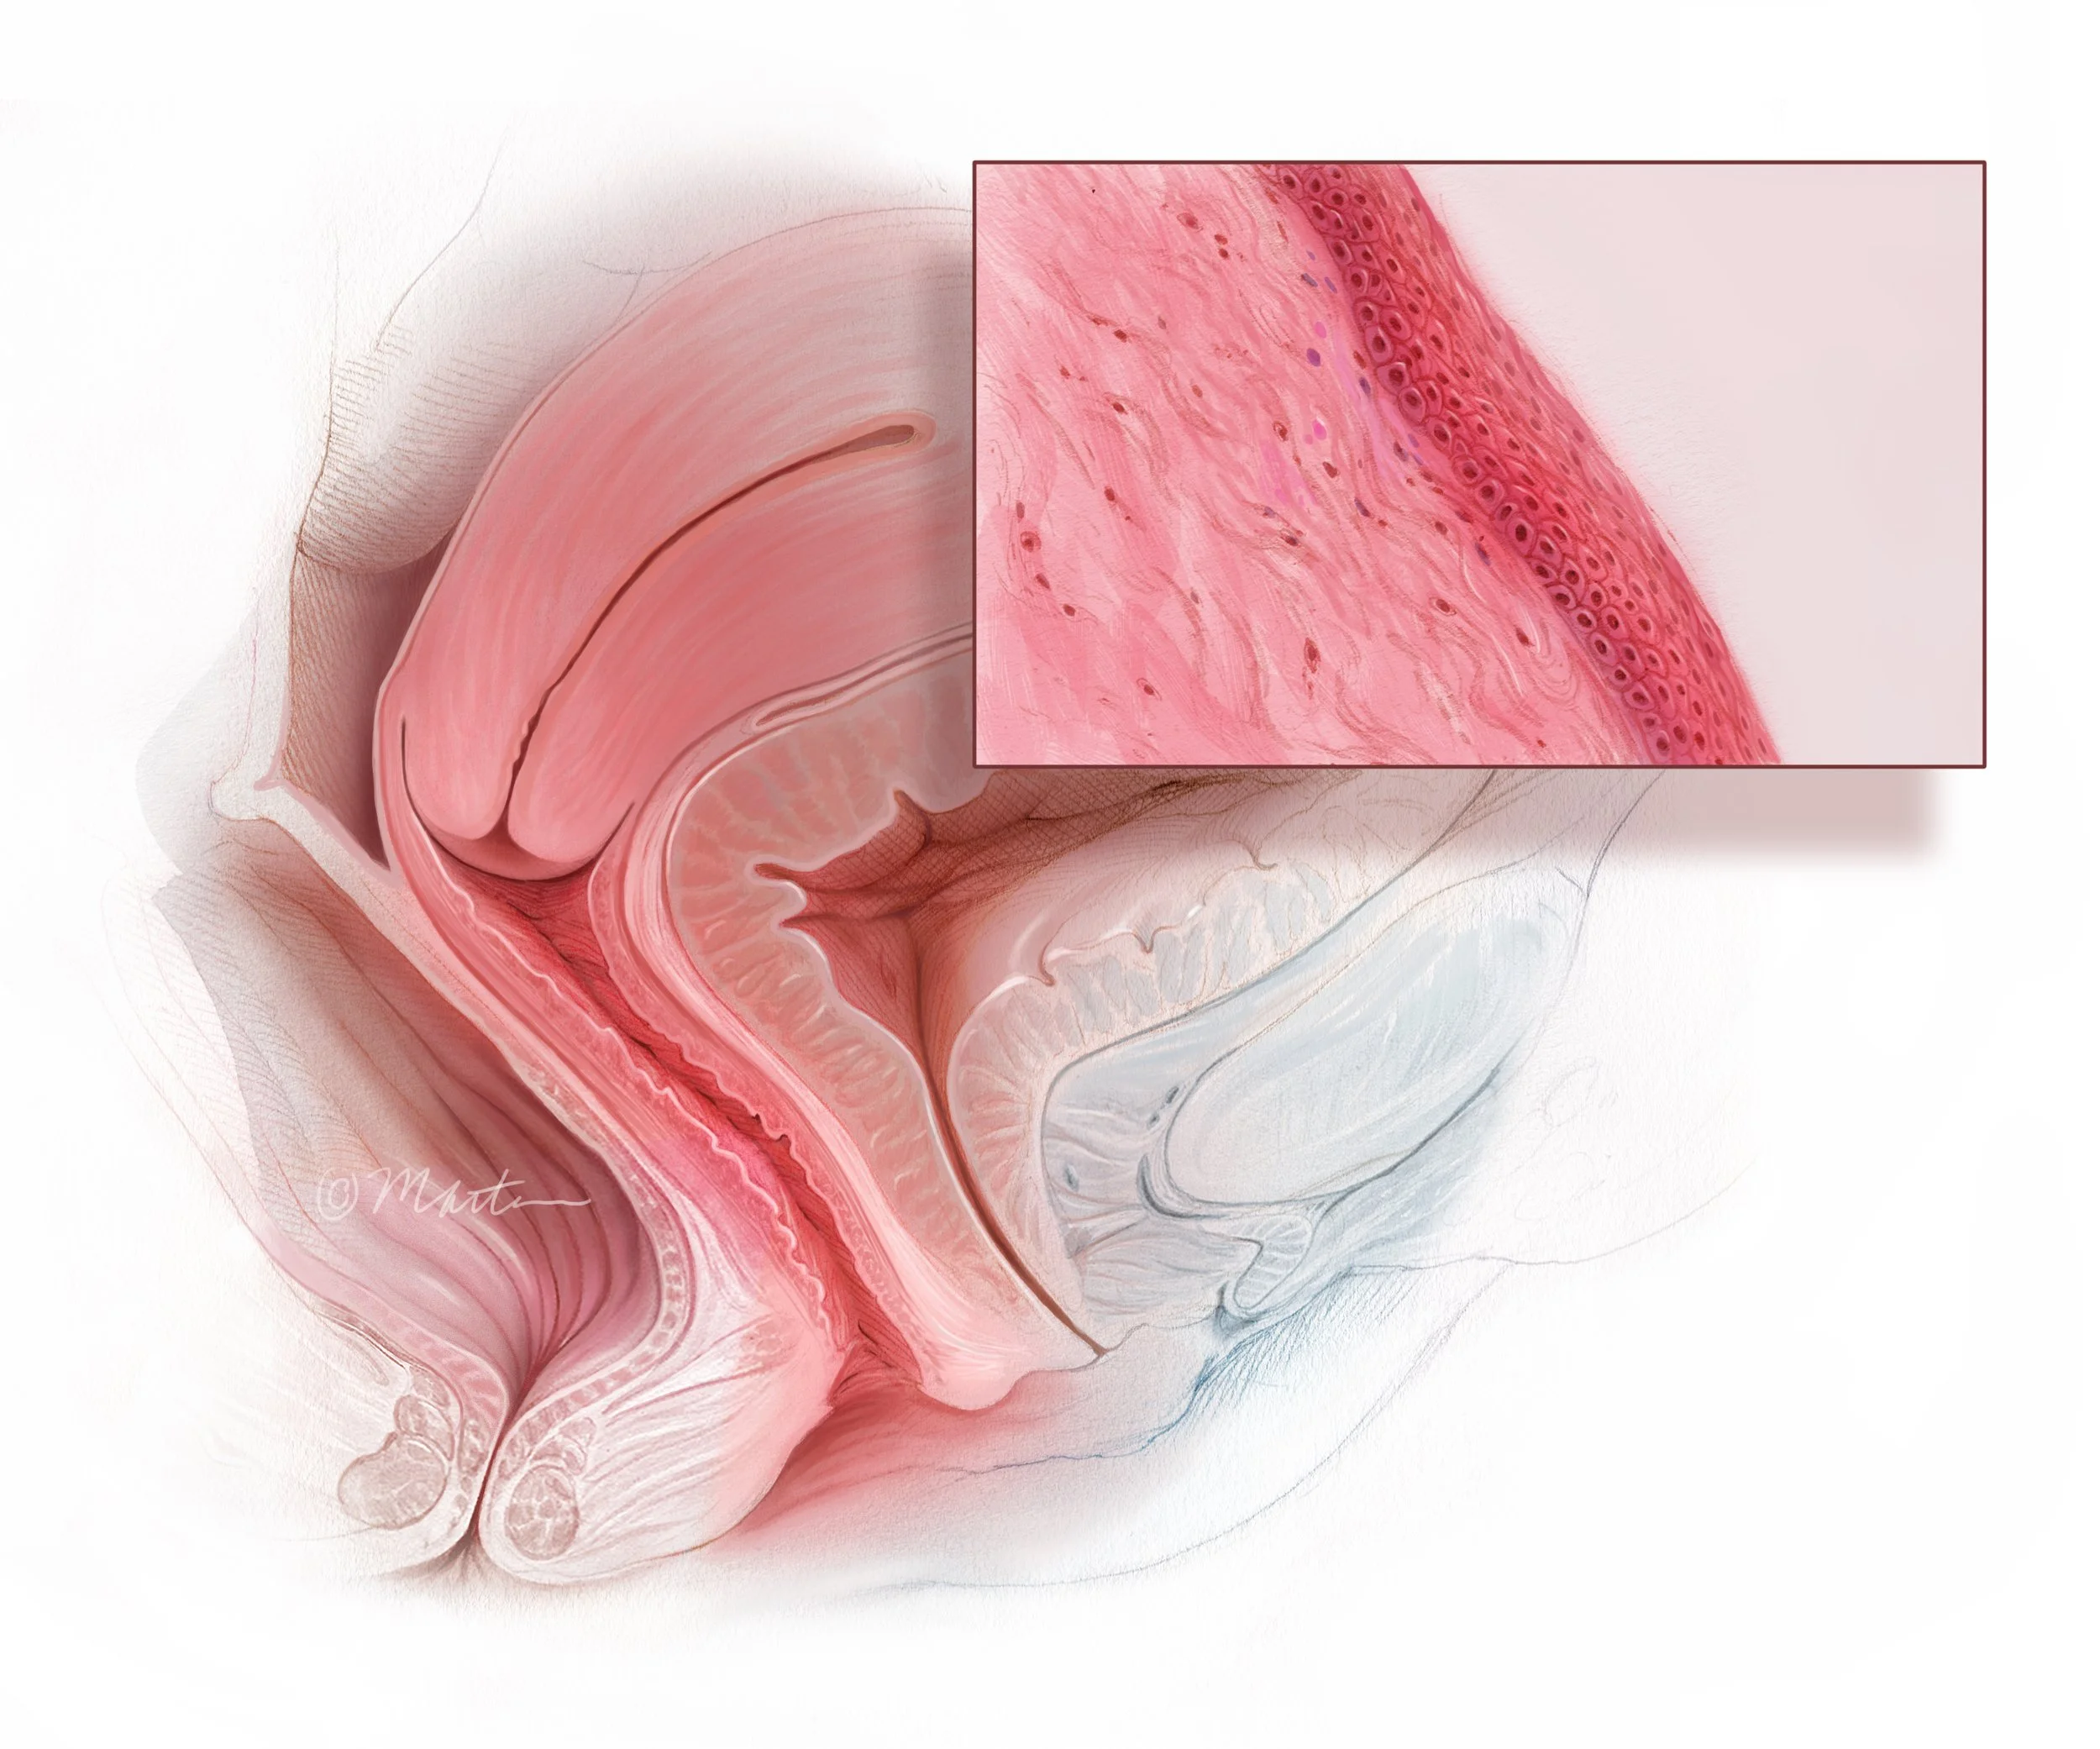

Vaginal Atrophy

Total Vaginal Hysterectomy